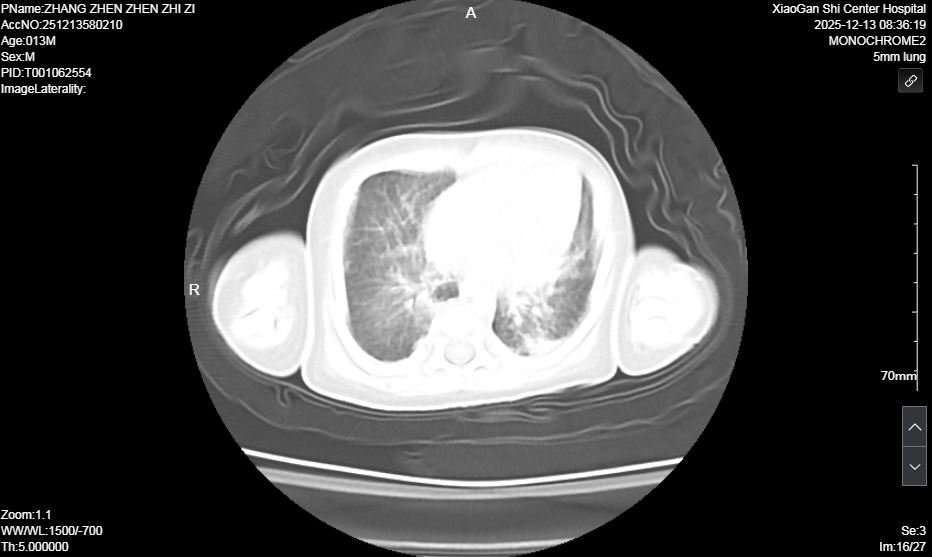

術前肺部超聲及CT均提示雙肺實變明顯